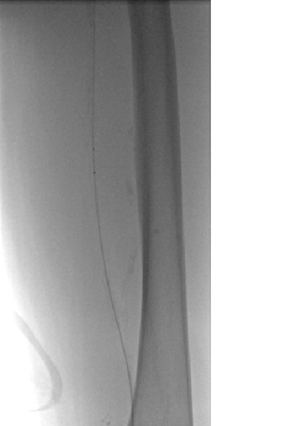

Venograma en posición de decúbito prono de la rama ilíaca izquierda que indica una estenosis causada por el tumor que comprime la uretra y la vena ilíaca externa izquierda.